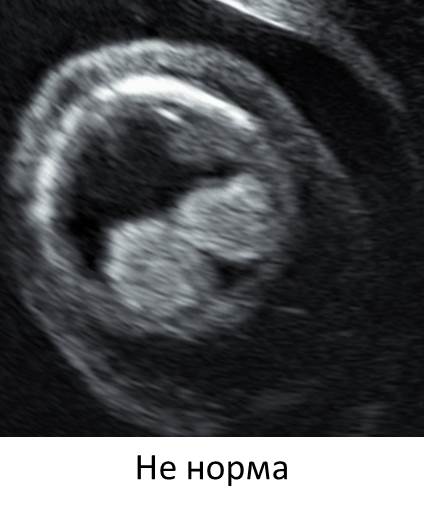

- Гиперэхогенные воды — очень патогномоничный признак дефекта костей свода черепа.

- Не визуализируется свод черепа — лобная, теменные кости.

- Мы видим затылочную кость с аномалией задней черепной ямки.

- Заключительный диагноз — акрания (мероакрания).

- Анэнцефалия/экзенцефалия ли это — по данному скану отдифференцировать нельзя.